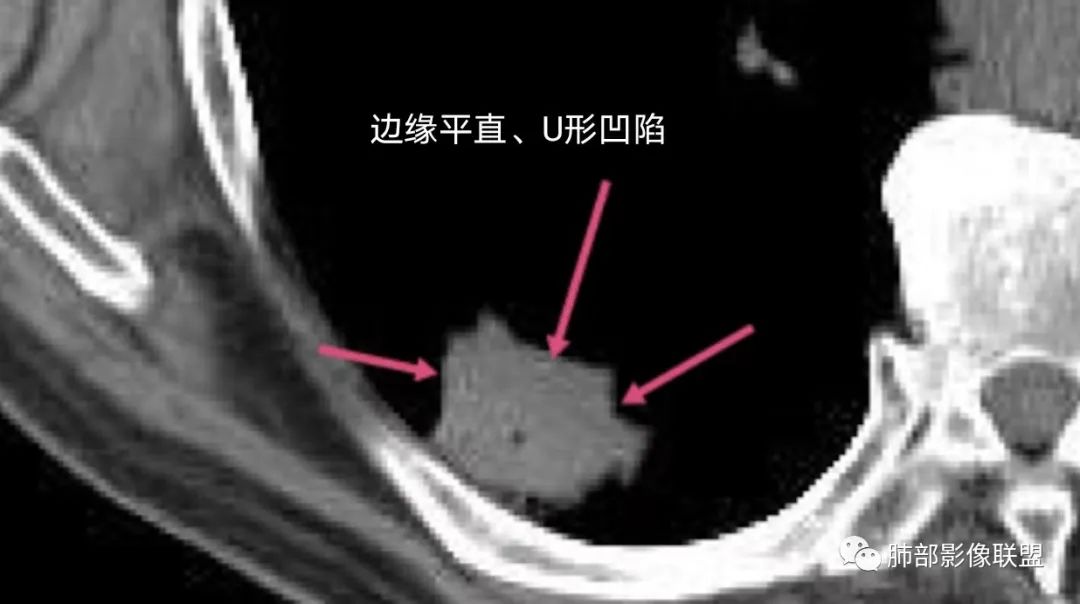

右肺下叶背段斑片影,边缘平直、局部膨隆,可见磨玻璃密度影,界清,胸膜牵拉,良恶性需要进一步鉴别,倾向隐球,鉴别粘液腺癌。

胸膜下结节,与胸膜平行,多结节融合,边缘模糊,直边征,考虑炎性肉芽肿,隐球,腺癌

右肺下叶背段实性结节,边缘分叶,较平直,长轴平行胸膜,胸膜增厚,考虑炎性假瘤,隐球菌,鉴别腺癌。

老年男性 右肺下叶胸膜下见一团状实性病灶+边缘磨玻璃,边缘形态不规则,,局部有平直,长轴平行于胸膜面,整体收缩力偏弱,邻近胸膜面轻度增厚,纵隔窗显示病灶内可见支气管充气,考虑炎性肉芽肿,隐球菌可能,鉴别黏液腺癌。

胸膜下结节,长轴与胸膜平行,边缘模糊,直边征胸膜凹陷牵拉不明显,考虑炎性肉芽肿,隐?鉴别腺癌。

右肺下叶后基底段胸膜下斑块影,边缘清楚,有平直和膨隆特点,周围清楚GGO,较模糊(似清非清,邻近见多发纯GGO结节,以肺腺泡分布,主体病灶与胸膜平行,收缩力弱,边缘见支气管充气征,首诊断炎性肉芽肿,抗炎治疗和查下隐球荚膜抗原两方面进行,另取旧片对比,与粘液腺Ca鉴别,最后经皮肺穿刺病理诊断!